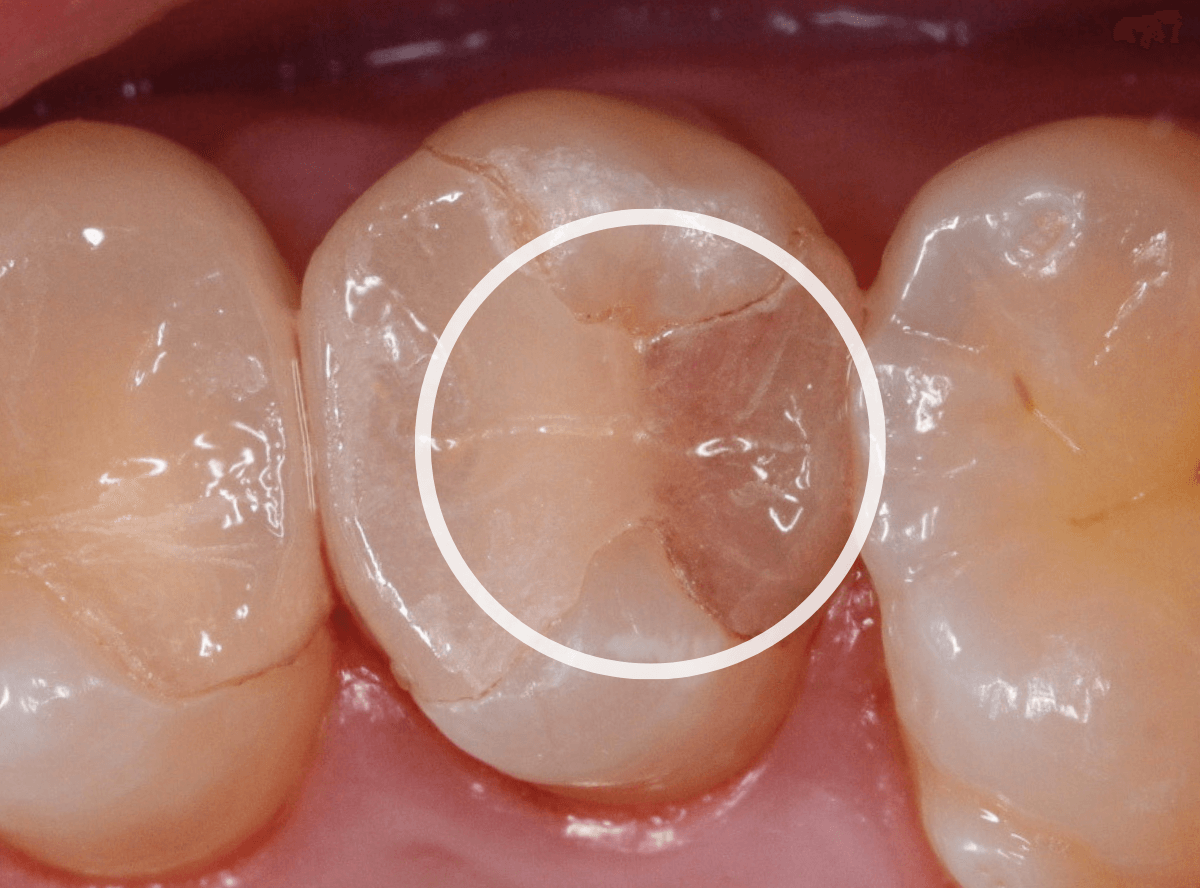

〇部が虫歯の部分です。

写真で見てわかるように、常に舌が歯に触っているような状況です。

このような場合、虫歯を見つけづらいですし、治療の難易度もあがります。

虫歯の治療を開始します。